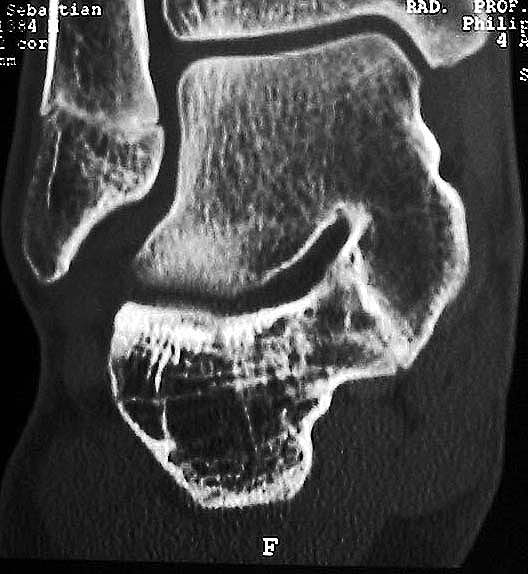

MRT und CT konkurrieren in der Fein-Darstellung der Knochenbrücke, der Beurteilung der nichtbetroffenen Anteile des Subtalargelenkes und der Sekundärveränderungen. Das MRT bietet den Vorzug, bindegewebige und knorpelige Strukturen (Abb. 2) und bei Einsatz von Kontrastmittel auch knöcherne Aktivierungsphänomene genau abzubilden; die knöcherne Feinstruktur und genaue Ausdehnung dagegen ist mit dem Dünnschicht-CT wesentlich exakter darstellbar (Abb.3). In manchen Fällen ist eine 3-D-Rekonstruktion des CT hilfreich. Besonders wichtig ist eine geeignete Schichtebenen-Wahl:

• Frontalschnitte etwa im rechten Winkel zur Auftrittsfläche und im Bereich des Subtalargelenkes bis weit nach dorsal geführt

• Sagittalschnitte

• Transversalschnitte besonders für das Talonaviculargelenk

• Spezielle schräge Schichtebenen in enger Absprache mit dem Radiologen

Diagnostisch sollte neben Röntgenübersichtsaufnahmen (indirekte radiologische Zeichen: Dorsaler Traktions-Osteophyt am Taluskopf, „talar beaking“; kontinuierliche Linie der Trochlea-tali-Kontur übergehend in die Sustentaculum-tali-Kontur, „C-Zeichen“ (Abb. 11) 10) immer die dreidimensionale Bildgebung eingesetzt werden. Das MRT (mit Kontrastmittel) kann die Struktur der Brückenbildung und z.B. die Qualität des Restgelenkes (Knorpel-Dicke) besonders gut abbilden; das Dünnschicht-CT zeigt die knöcherne Feinstruktur im Bereich der Coalitio und den oft sehr schrägen Spalt-Verlauf im Frontalschnitt dagegen häufig genauer. Meist findet sich die Überbrückung im Bereich der medialen Facette; die Schichten sollten jedoch bis weit nach dorsal beurteilt werden, da ansonsten dorsomediale Formen übersehen werden können. Rozansky et al 7 unterschieden fünf morphologische Typen auf der Basis von 3-D-CT-Rekonstruktionen. Allerdings ist eine prognostische Zuordnung bisher nicht möglich.